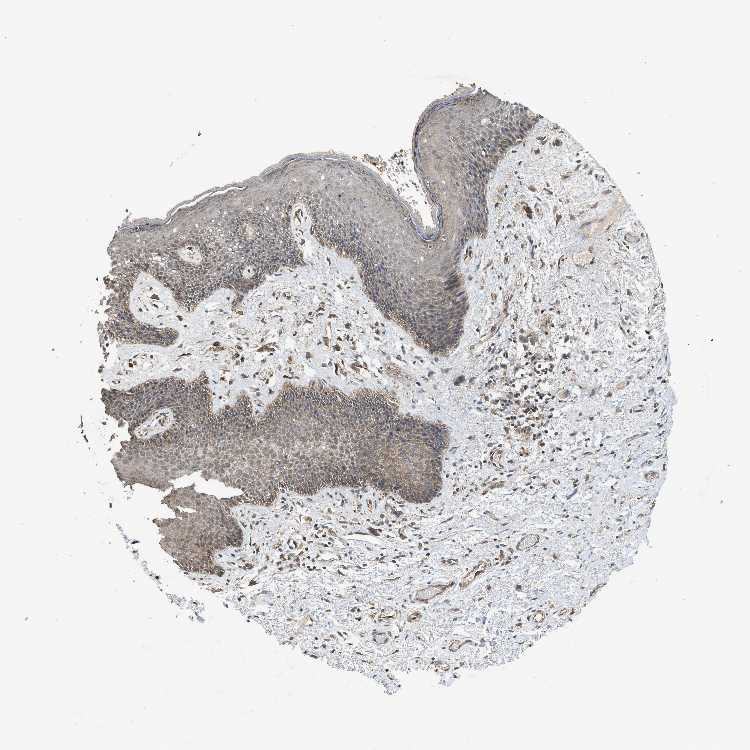

SKIN 1 - Antibody stainingi

Antibody staining in the annotated cell types in the current human tissue is reported as not detected, low, medium, or high, based on conventional immunohistochemistry profiling in selected tissues. This score is based on the combination of the staining intensity and fraction of stained cells.

Each image is clickable and will lead to virtual microscopy that enables deeper exploration of all samples and also displays staining intensity scores, fraction scores and subcellular localization as well as patient and tissue information for each sample.

Antibody HPA038135Antibody HPA038136

Langerhans LowNot detected

Fibroblasts Not detectedNot detected

Keratinocytes LowLow

SKIN 2 - Antibody stainingi

Antibody HPA038135Antibody HPA038136Antibody CAB017187

Epidermal cells MediumMediumMedium